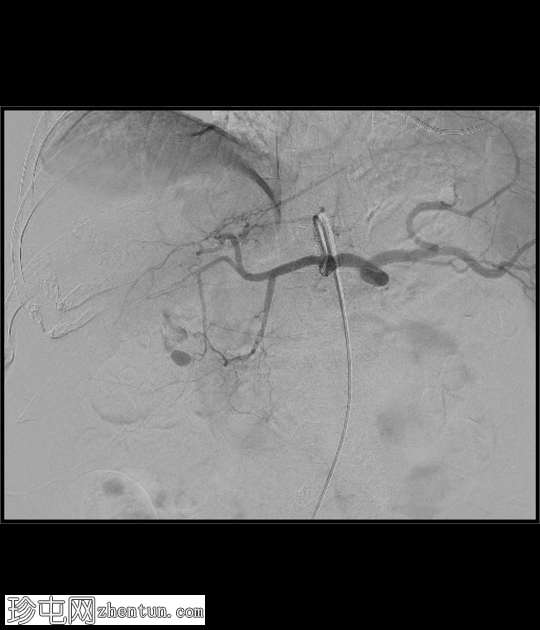

DSA

4.png

正面

腹腔干

5.png

血管造影证实存在胆囊动脉假性动脉瘤,并伴有活动性出血征象。

行胆囊动脉栓塞术,术后血管造影显示疗效满意。